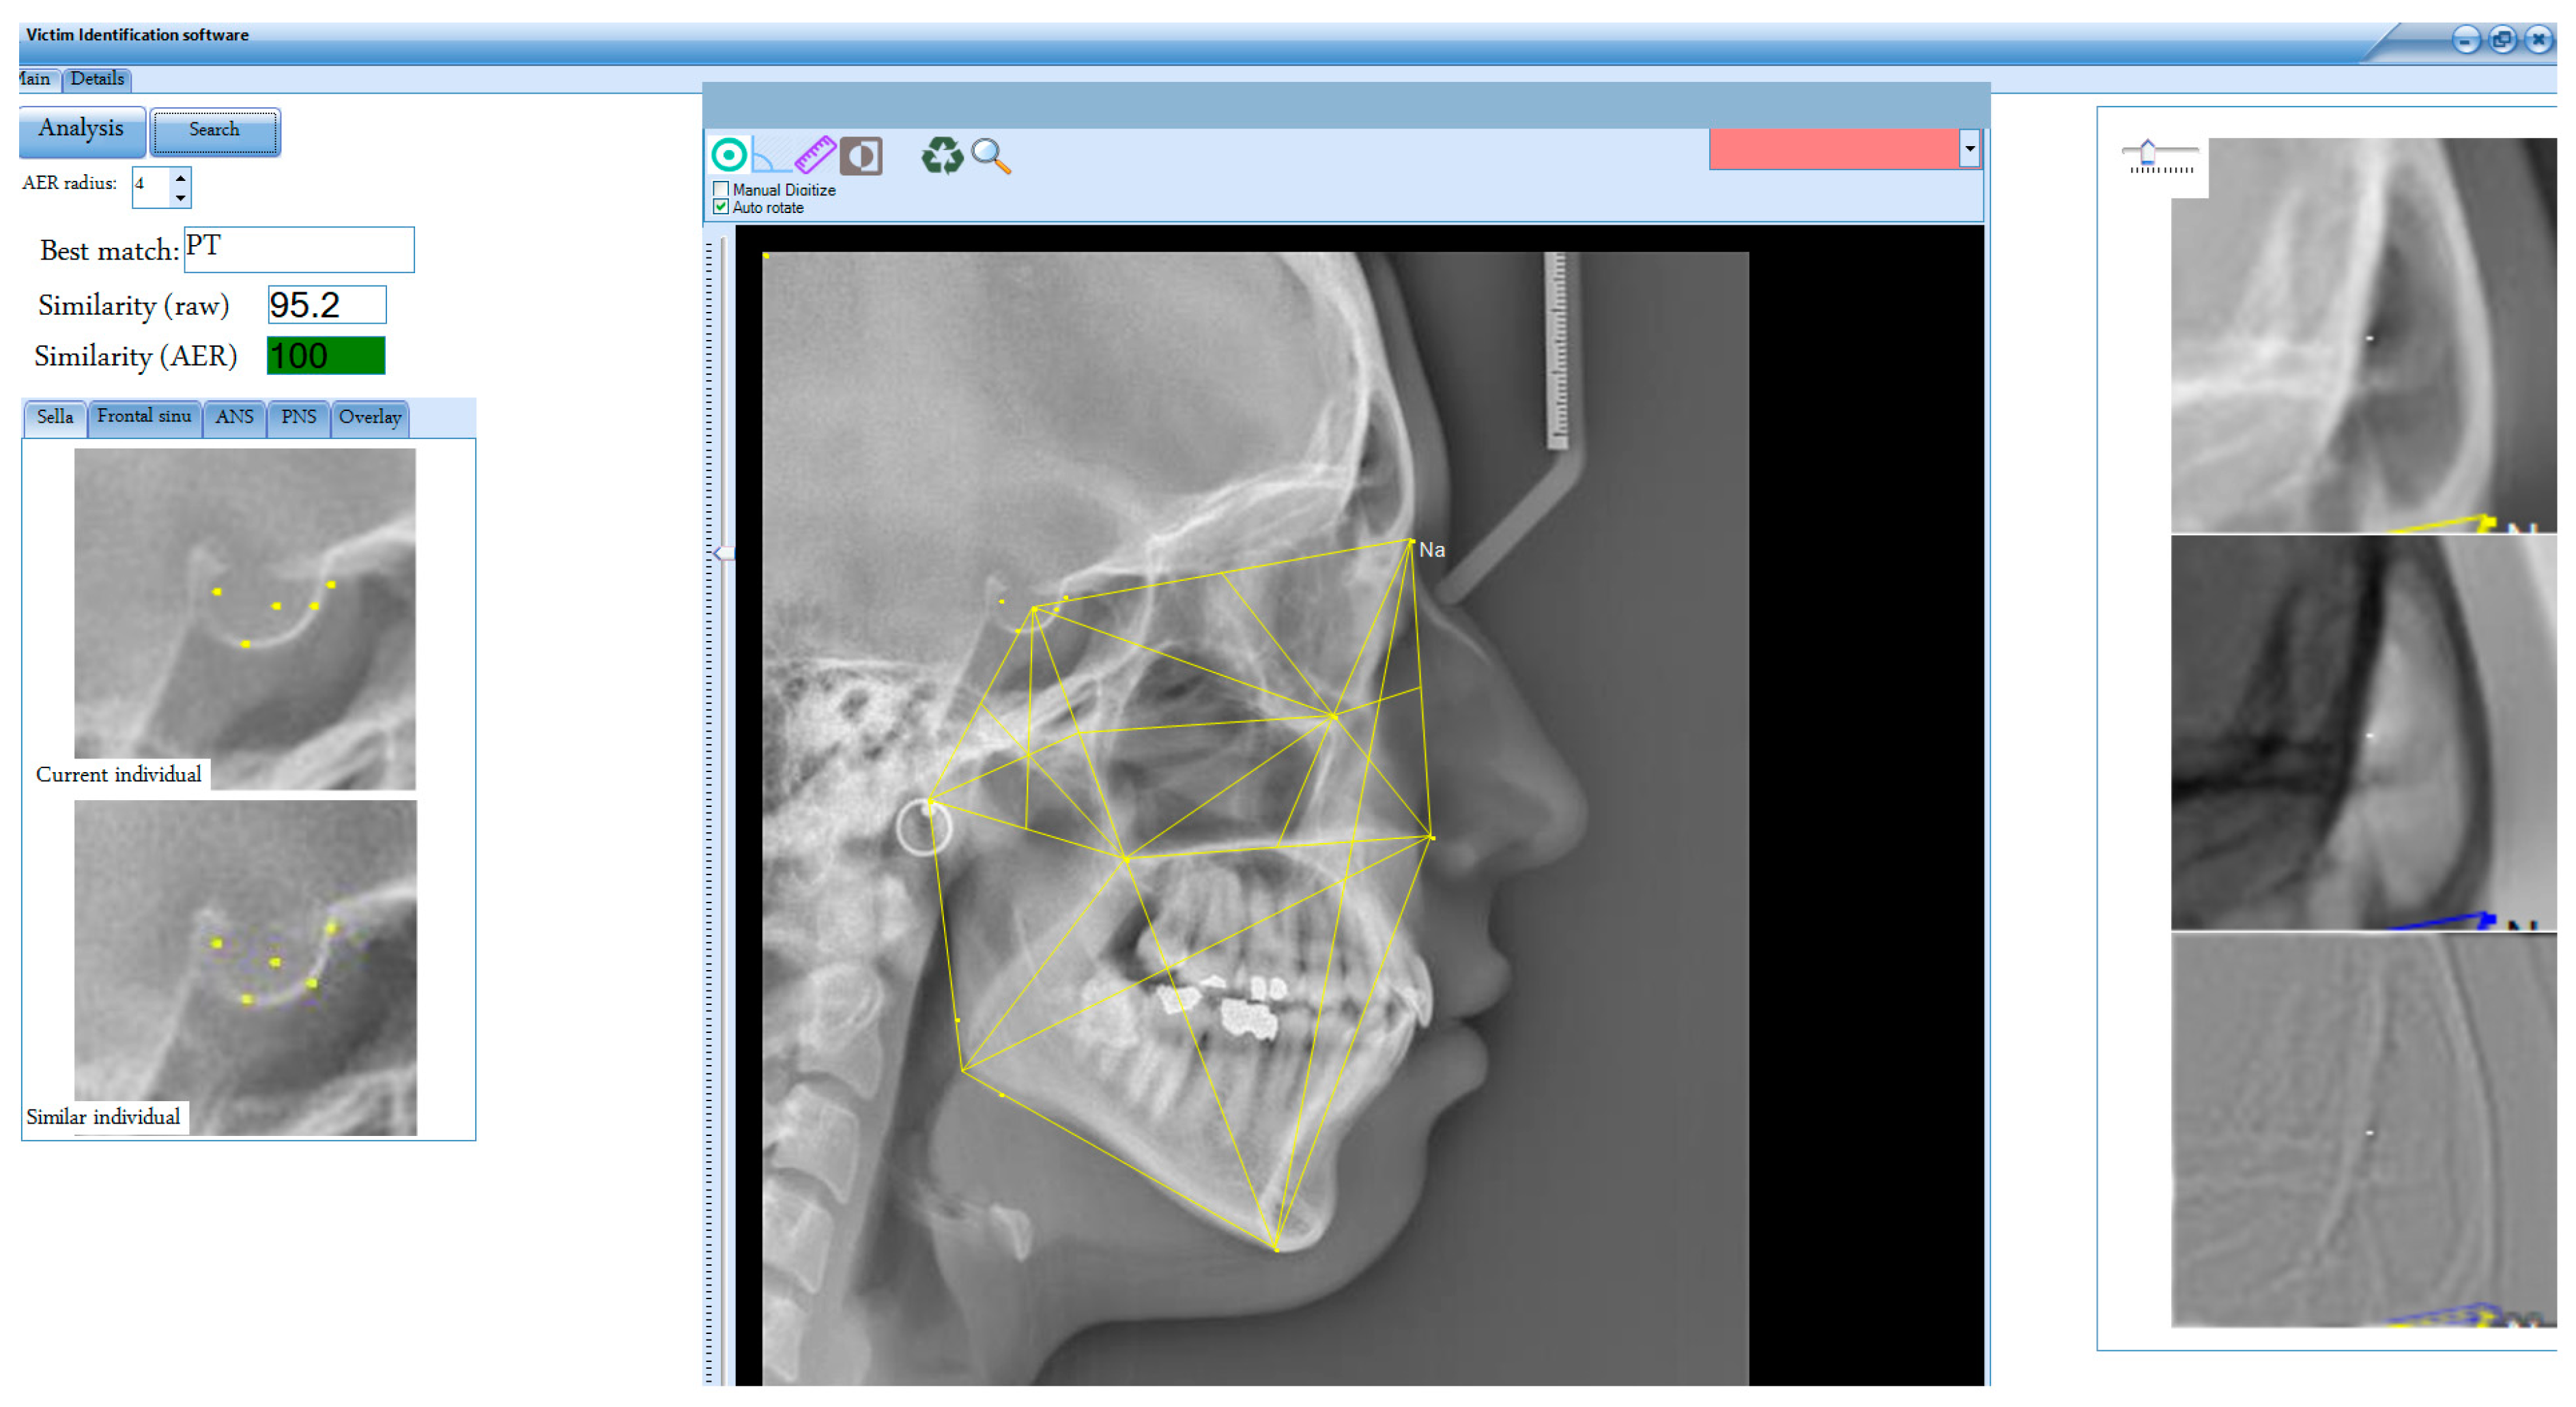

| Parameter | Definition | Result |

|---|---|---|

| Age (years) | Mean age ± standard deviation (SD) of samples | 22.21 ± 4.5 |

| Similarity | Mean similarity ± SD | 91.02 ± 2.6% |

| Similarity_AER | Mean similarity ± SD after applying the AER function | 98.10 ± 3.37% |

| Accuracy | (TP + TN)/(TP + TN + FP + FN) | 0.975 |

| Sensitivity | TP/(TP + FN) | 0.977 |

| Specificity | TN/(TN + FP) | 0.952 |